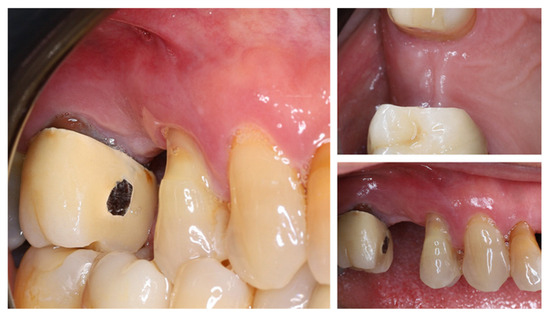

One year after tooth extraction, the clinical examination revealed complete soft tissue healing (Figure 3). At the buccal aspect of the alveolar ridge, the usual post-extraction horizontal ridge defect was observed. Post-extraction alveolar ridge collapse is a common clinical condition after tooth extraction. Horizontal and vertical bone loss can reach up to 60% within 2 years after tooth extraction, with most occurring within the first year after extraction.

Figure 3.

Clinical status of the patient after healing—vestibular and occlusal view.

This volume loss is most pronounced in the bucco-lingual direction and occurs more frequently in the absence of adequate buccal wall thickness of the dental alveolus (<1 mm) [24].

New cone-beam computed tomography (CBCT), performed to assess the morphology of the healed ridge, demonstrated a complete healed crestal bone with a bucco-lingual width of 8.2 mm. In the sagittal plane, the total vertical bone height measured 11.5 mm, suggesting adequate dimensions for implant placement without additional bone augmentation. The bone density measurement presented a high BMD value in the apical part of the crest while the density in the newly formed bone was relatively low (Figure 4).

Figure 4.

One year after autogenous healing of the extraction site.